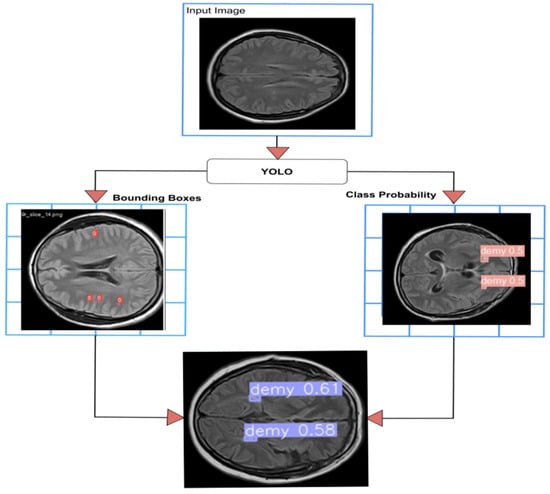

4.2.3. YOLO Model for Detecting WMH Lesions

- The curves of “train/box_loss” and “val/box_loss” show the training and validation loss related to the bounding box predictions. As the loss function decreases, it signifies that the network is effectively learning and enhancing its capability to precisely predict well-fitted bounding boxes.

- The “train/seg_loss” and “val/seg_loss” represents the training and validation segmentation loss.

- The “train/cls_loss” and “val/cls_loss” refer to training classification loss, which evaluates the classification accuracy of each predicted bounding box.

- The “train/dfl_loss” and “val/dfl_loss” indicate the training distribution focal loss, indicating the model’s confidence in predictions.

- The graph of “metrics/precision(B)” and “metrics/precision(M)” indicates the precision for bounding box predictions and precision for mask predictions, respectively.

- The “metrics/recall(B)” and “metrics/recall(M)” are the recall for bounding box predictions and recall for mask predictions, respectively. This indicates the ability to identify true positive masks.

- The “metrics/mAP50(B)” and “metrics/mAP50(M)” are the mean average precision at 50% IoU (Intersection over Union) for bounding boxes and for masks, respectively.

- The “metrics/mAP50-95(B)” and “metrics/mAP50-95(M)” are the mean average precision at IoU thresholds from 50% to 95% for bounding boxes and for masks, respectively.

4.3.1. YOLOv8 Model for Detection and Classification